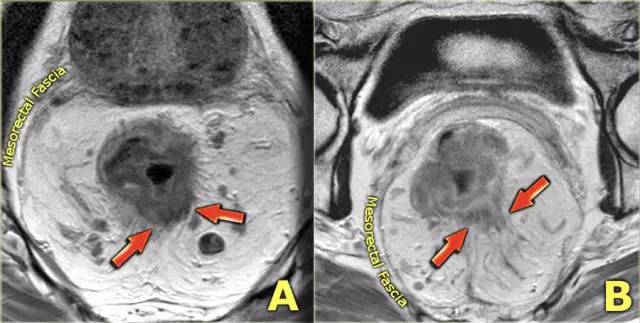

T3 分期,累及 MRF

在 T3 肿瘤的描述中,报告应包括肿瘤边缘和 MRF 之间的最短距离。MRF 阳性导致局部复发的风险增加(当肿瘤边缘和 MRF 之间的距离小于 1 mm 时,MRF 被认为是阳性)。

图 8 T3 直肠癌 MRF+